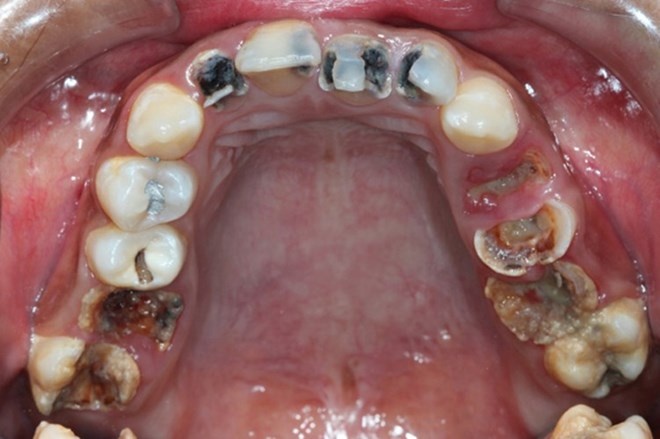

Theo kết quả điều tra răng miệng gần đây cho thấy, toàn quốc có trên 60% người bị sâu răng. Trung bình 18 tuổi đã có khoảng 2,84 người bị sâu răng; 45 tuổi đã sâu 8,93 răng. Đặc biệt tỷ lệ mất răng do sâu cũng đáng báo động.

Cụ thể 18 tuổi trung bình đã bị mất một cái răng, 45 tuổi đã mất 6,64 cái răng. Đặc biệt, có khoảng 85% trẻ em từ 6-8 tuổi bị sâu răng, mỗi trẻ trung bình có tới 6 răng sâu và phần lớn bệnh nhân mắc bệnh không được điều trị kịp thời. Nếu không được điều trị sẽ ảnh hưởng đến sức khỏe, thẩm mỹ.

| 85% trẻ từ 6-8 tuổi bị sâu răng. |